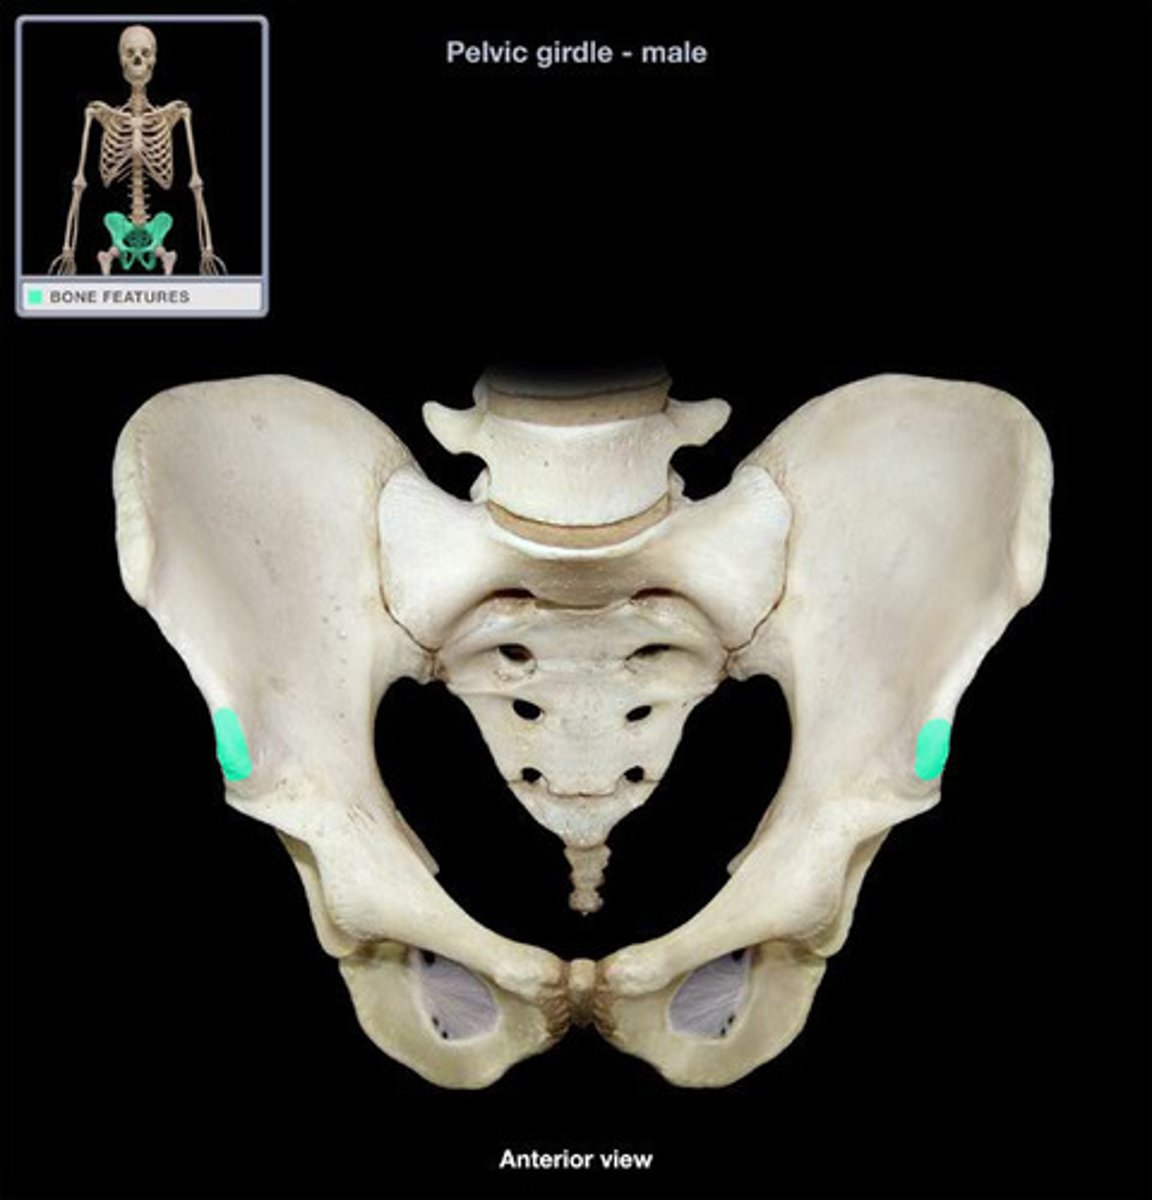

bony pelvis

2 coxal bones, sacrum, coccyx

ilium

weight bearing during sitting

pubis

The medial anterior portion of the pelvis

ischium

the lower, posterior portions of the pelvis

iliac crest

upper margin of iliac bones

posterior superior iliac spine

the sharp posterior end of the iliac crest

posterior inferior iliac spine (PIIS)

a bony projection located inferior to the posterior superior iliac spine

anterior superior iliac spine

origin of sartorius

anterior inferior iliac spine (AIIS)

origin of rectus femoris

iliac fossa

The broad, slightly concave inner surface of the ilium.

Acetabulum

large socket in the pelvic bone for the head of the femur

acetabular notch

deep notch in the inferior part of the brim

greater sciatic notch

allows blood vessels and the large sciatic nerve to pass from the pelvis posteriorly into the thigh

ischial tuberosity

receives the weight of the body when sitting

body of ischium

Makes up all of the ischium superior to the tuberosity

ramus of ischium

joins the inferior ramus of the pubis anteriorly

obturator foramen

opening in hip bone formed by the pubic and ischial rami

body of pubis

origin of adductor longus

arcuate line

a ridge of bone that runs inferiorly and anteriorly from the auricular surface, forms pelvic brim

iliopubic eminence

marks the point of union of the ilium and the pubis just lateral to the arcuate line

pubic tubercle

An attachment point for the inguinal ligament.

superior ramus of pubis

origin of pectineus

inferior ramus of pubis

origin of adductor brevis

pubic symphysis

cartilaginous joint at which two pubic bones fuse together